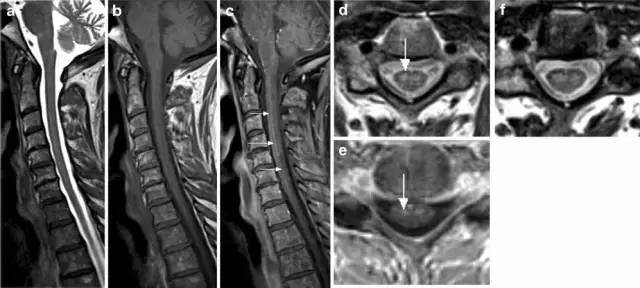

病例1:77岁女性,脊髓前动脉综合征。表现为进行性四肢瘫,剧烈颈部疼痛向双上肢放射。MRI T2(图a)显示纵向高信号,T1(图b)及强化显示脊髓腹侧轻度不均匀强化(铅笔画样;图c箭头)。T2轴位(图d,f)显示C3/4水平脊髓前角对称性高信号(图d箭头为蛇眼征;图e箭头显示轻度强化),病变扩展到C5水平,累及脊髓后动脉分布区。